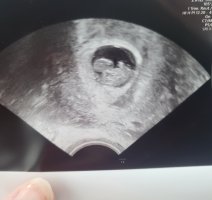

Ååh så kjekt! Lite som er bedre enn det!Så er uke 8+0, ble satt en uke frem Vis vedlegget 439187